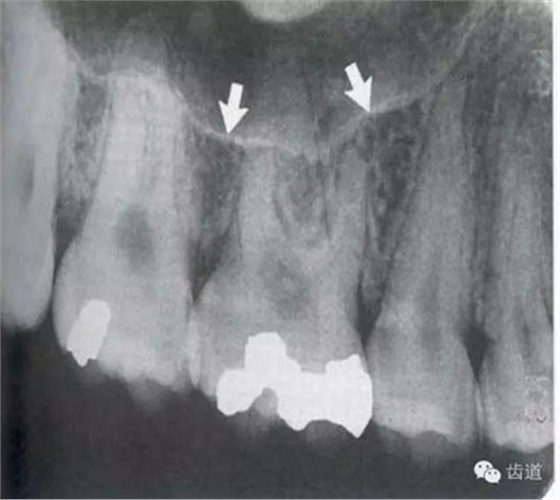

在投照上頜磨牙根尖片時(shí),經(jīng)常可以看到牙根上方有一密度低的影像,為上頜竇的一部分,邊緣環(huán)繞以密度高的線狀影像,為上頜竇壁致密骨層。有時(shí)可見(jiàn)上頜竇的分隔。

可在第一、二磨牙根尖上方或重疊在牙根上為近似三角形或半圓形密度高的影像。

常在上頜第二、三磨牙的牙冠區(qū)域有一較牙密度稍低由后伸向前方的三角形影像。

在最后一個(gè)磨牙遠(yuǎn)中區(qū)域,其邊緣向后上,X線片上常呈稀疏的網(wǎng)狀結(jié)構(gòu),為正常疏松區(qū)。

在上頜結(jié)節(jié)后方,呈長(zhǎng)條狀邊緣整齊、寬約0.2cm、長(zhǎng)約1cm、直的或下端略向后方彎曲的密度稍高的影像。

在第一磨牙腭側(cè)根上方呈圓形密度低影像。